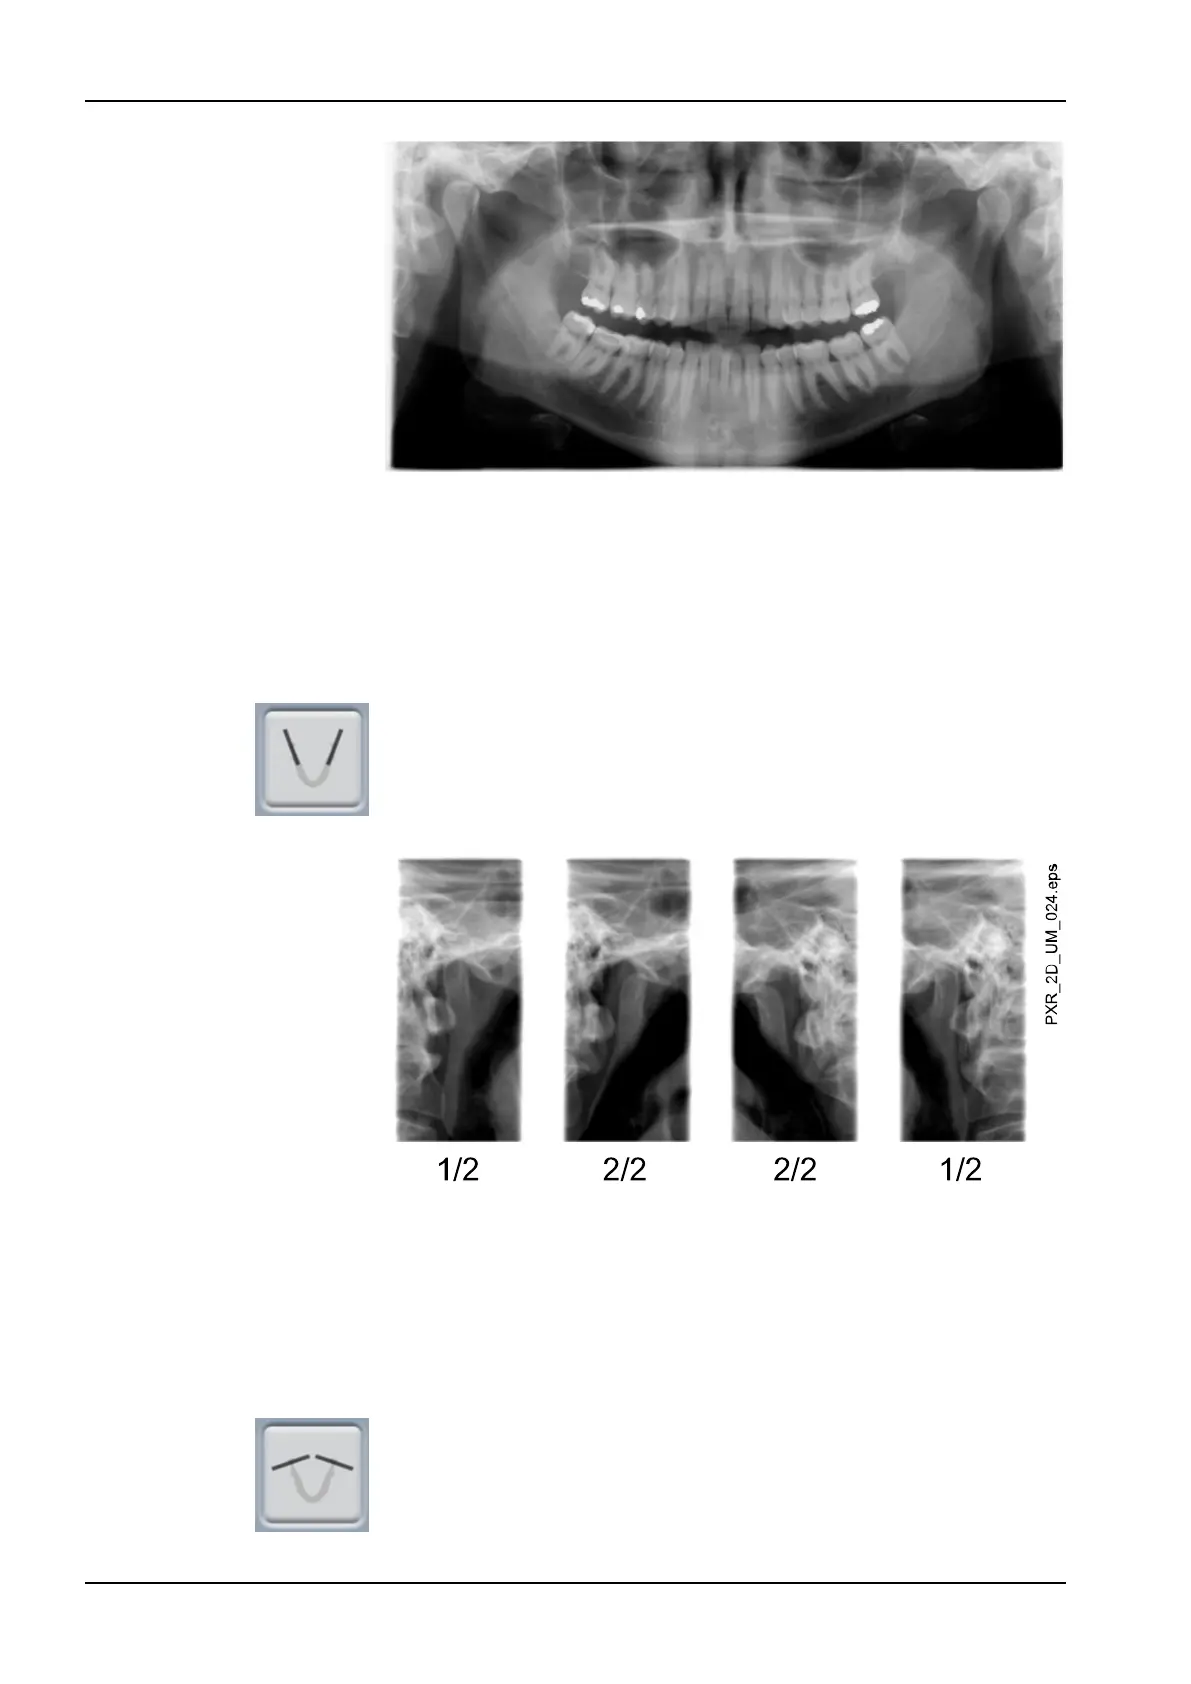

4.2.1 Double lateral

Lateral exposures of closed (1/2) and open (2/2) temporomandibular joints.

4.2.2 Double posteroanterior

Posteroanterior exposures of closed (1/2) and open (2/2)

temporomandibular joints.